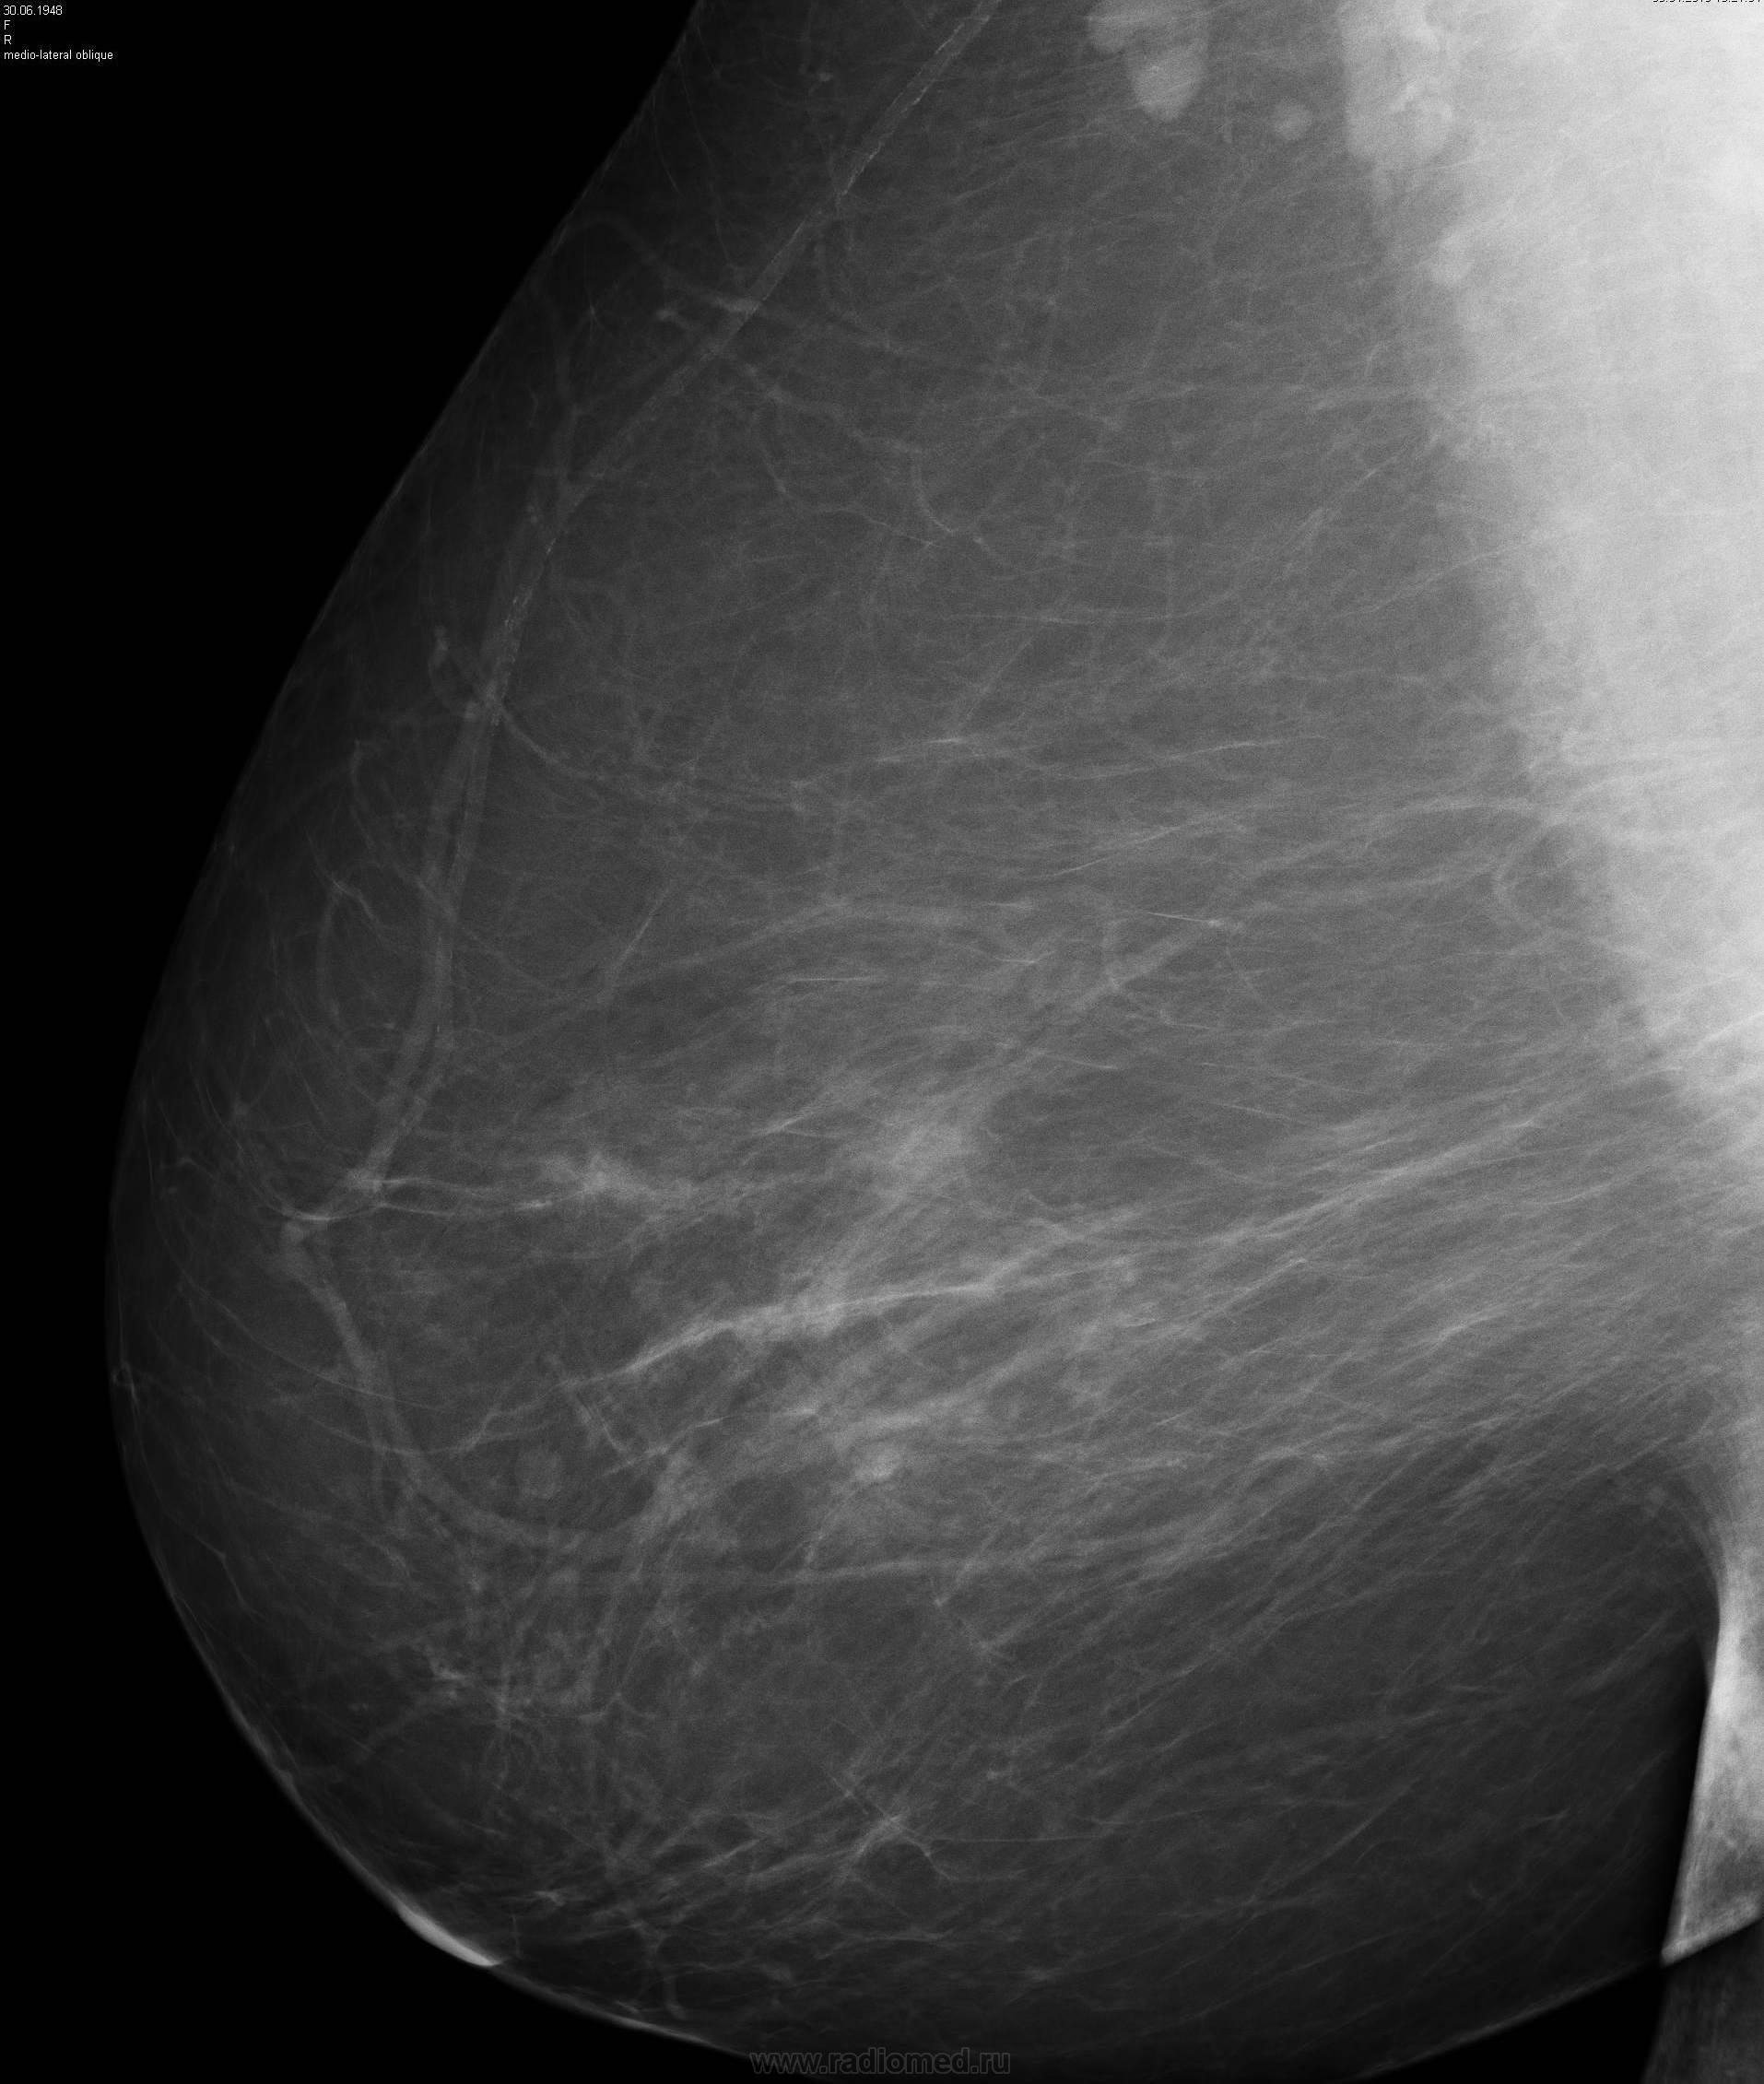

Уважаемы коллеги. Хочу представить интересный случай. Женщина 65лет 2 года назад травмировала левую молочную железу, год назад травмировала повторно (в том самом месте).Однократно были кровяные выделения из соска левой железы. На момент обращения в левой железе пальпируется узловое образование. Я поставил "зло

Почему зло? Кисты и кисты. Ну, глыбки извести (дегенеративные) в одной. На соно вроде внутренние стенки без разрастаний. Скиалогически зла не вижу. Отметтье плиз зону сомнений.

Кисты малых размеров- почему интенсивность такая высокая? Кисты обычно слабоинтенсивные.

Потому, что "2 года назад травмировала левую молочную железу, год назад травмировала повторно (в том самом месте).Однократно были кровяные выделения из соска левой железы", т.е. "Это может быть организовавшейся кровью"

Принимаю, обызвествленная кровь выглядит не так, как в начале ветки. Однако, там почти все кисты гиперденсные, что ж теперь полифокальный рак заподозрить во всех кистах. Петрификаты-то не плеоморфные, и даже не микро, и даже не кластер. Я так понимаю, будет еще и верификация наблюдения?

Не смотря дискуссию, сначала решила себя проверить - по моему эта "киста" с кальцинатами в ее проекции демонстрирует признаки инвазивного роста

На Rcc смушает утолщенная кожа ареолы, слабая ее втянутость (окромя самого локального фиброза).

Кровоизлияния располагаются и обызвествляются по-разному. Одно - в виде плоскости, и выглядит полупрозрачным. Другое - в виде локальных полостей с массивным кальзинозом, а часть содержимого еще "недокальцинировалась".